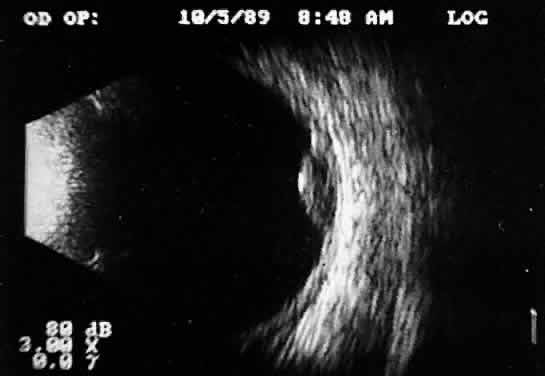

Fig. 5. Contact B-scans. A. Heavy formed vitreous hemorrhage obscuring choroidal mass. B. Voluntary movement of the globe causes the formed vitreous to shift, permitting easy detection of the ocular wall mass.